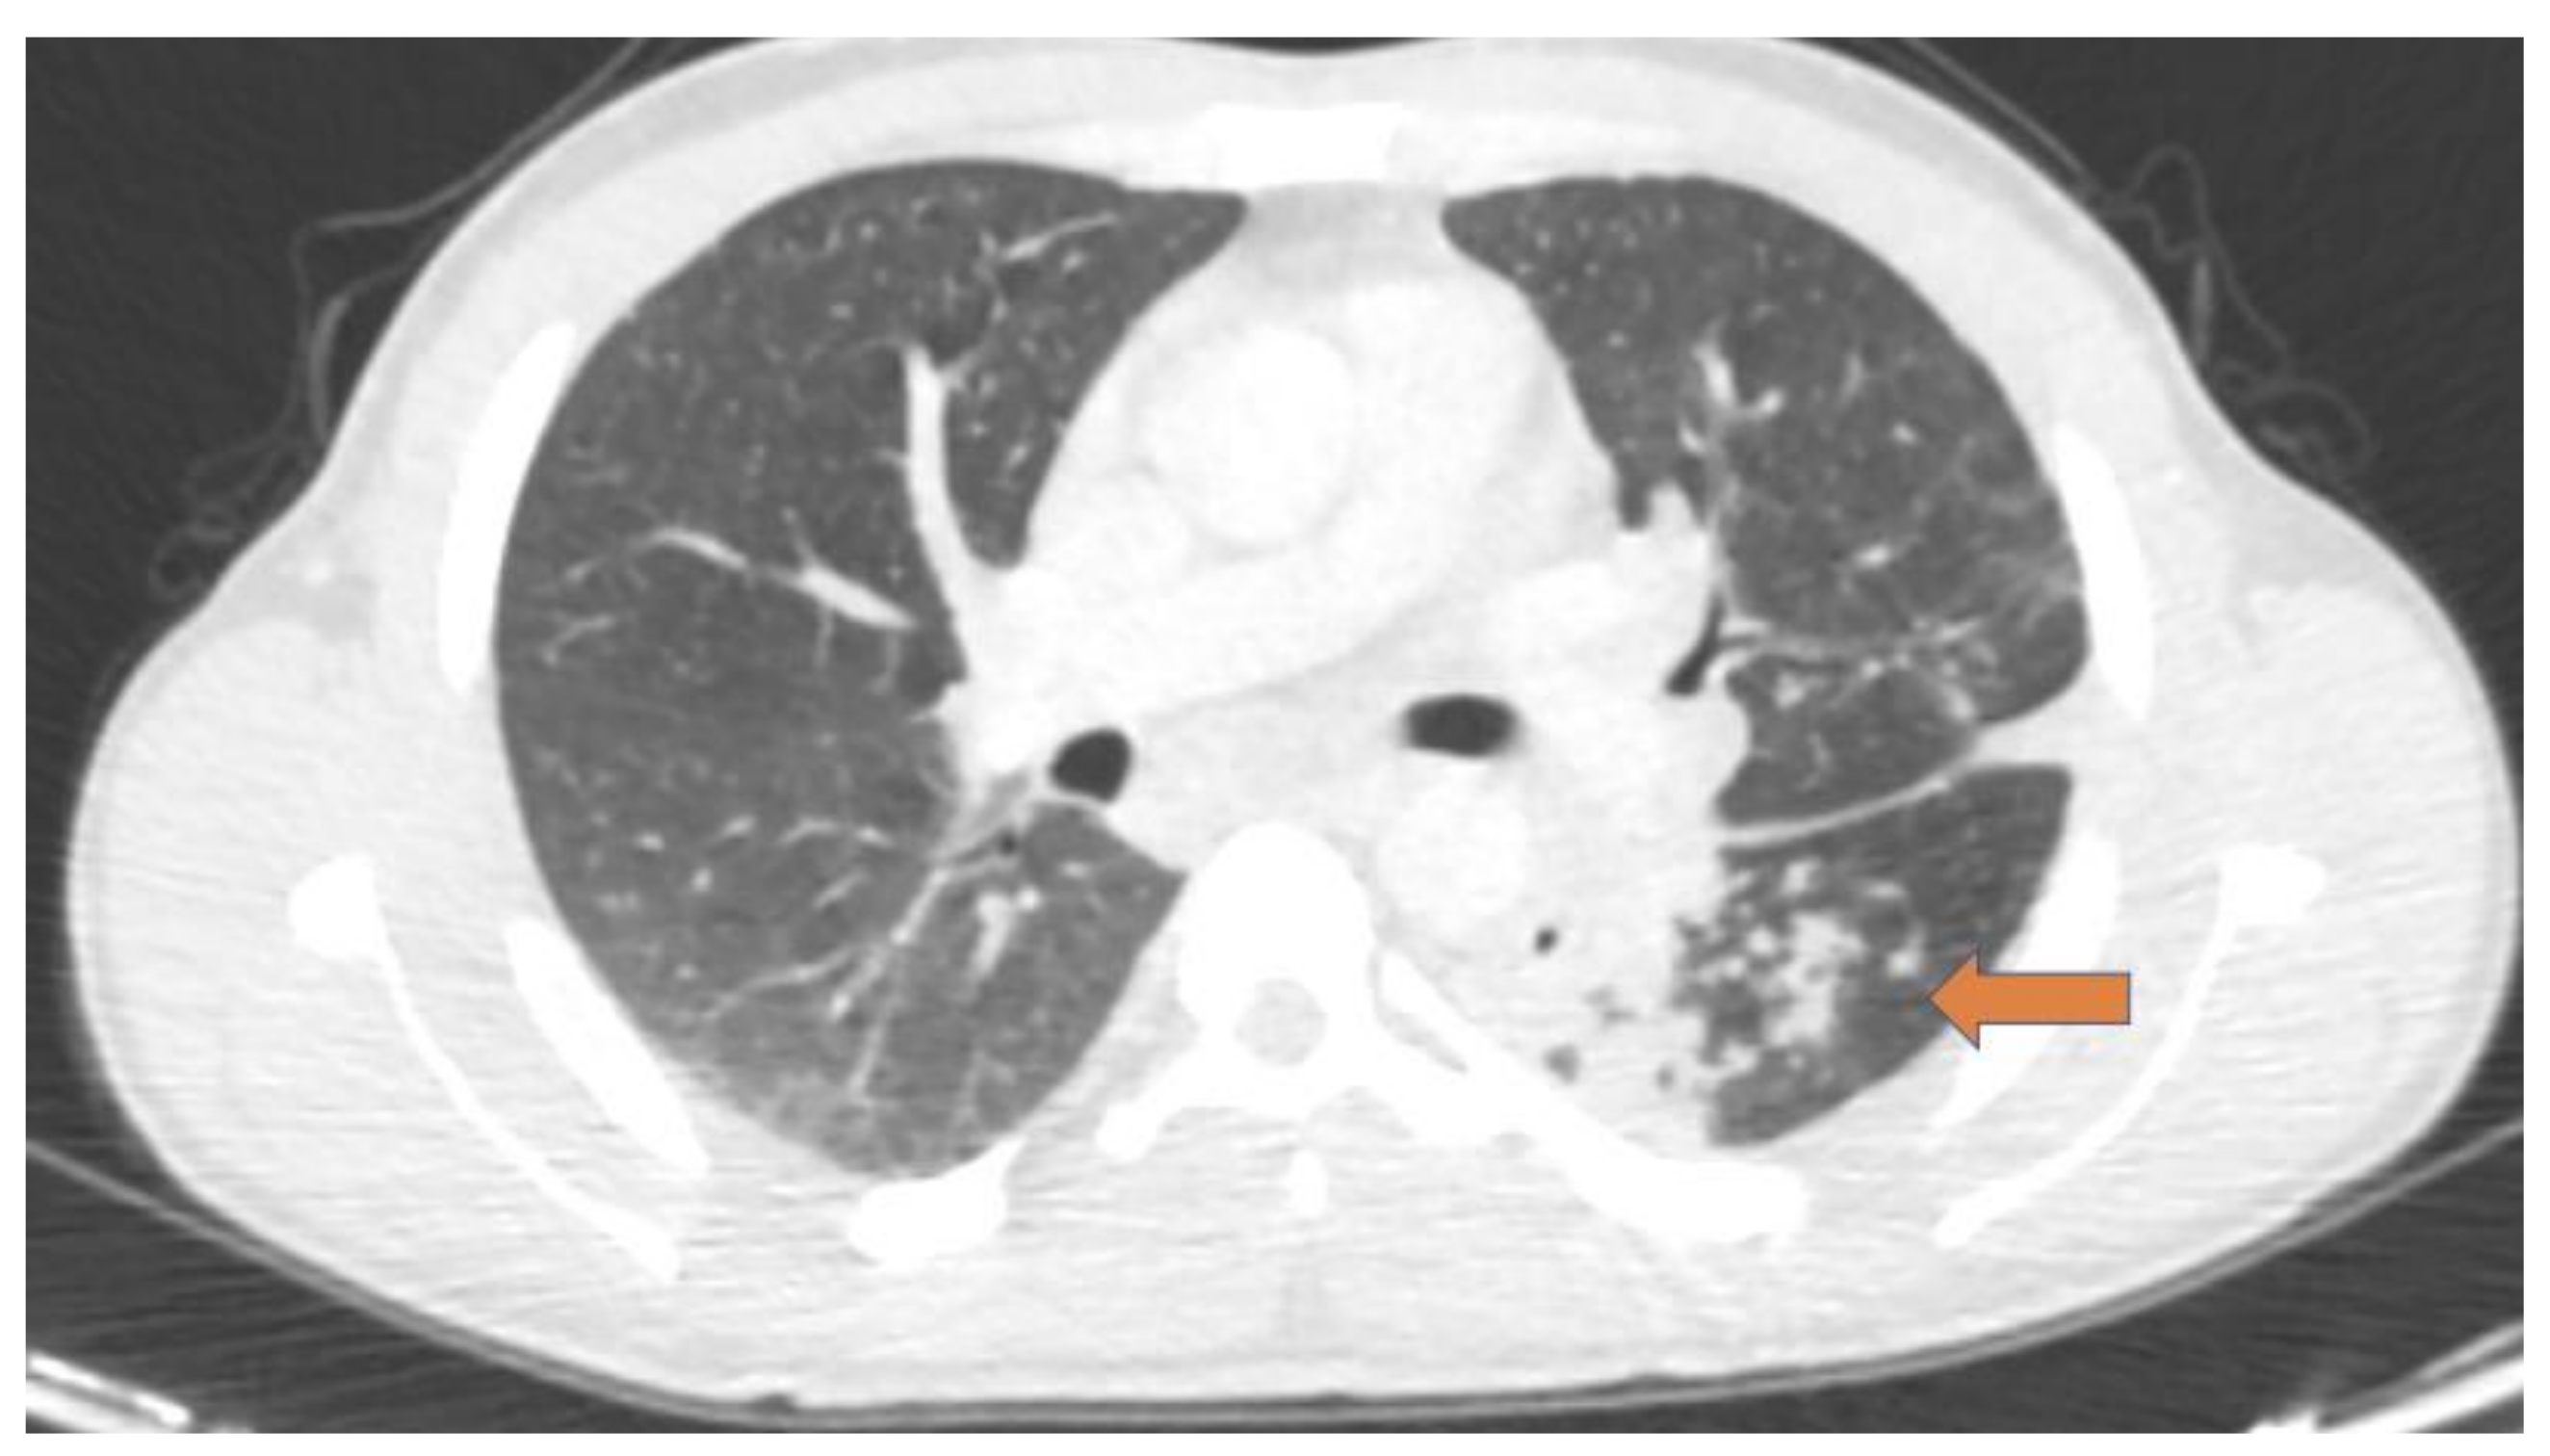

- Foti, G.; Gobbi, F.; Angheben, A.; Faccioli, N.; Cicciò, C.; Carbognin, G.; Buonfrate, D. Radiographic and HRCT imaging findings of chronic pulmonary schistosomiasis: Review of 10 consecutive cases. BJR Case Rep. 2019, 5, 20180088. [Google Scholar] [CrossRef]

- Gobbi, F.; Buonfrate, D.; Angheben, A.; Beltrame, A.; Bassetti, M.; Bertolaccini, L.; Bogina, G.; Caia, S.; Duranti, S.; Gobbo, M.; et al. Pulmonary nodules in African migrants caused by chronic schistosomiasis. Lancet Infect. Dis. 2017, 17, 159–165. [Google Scholar] [CrossRef]